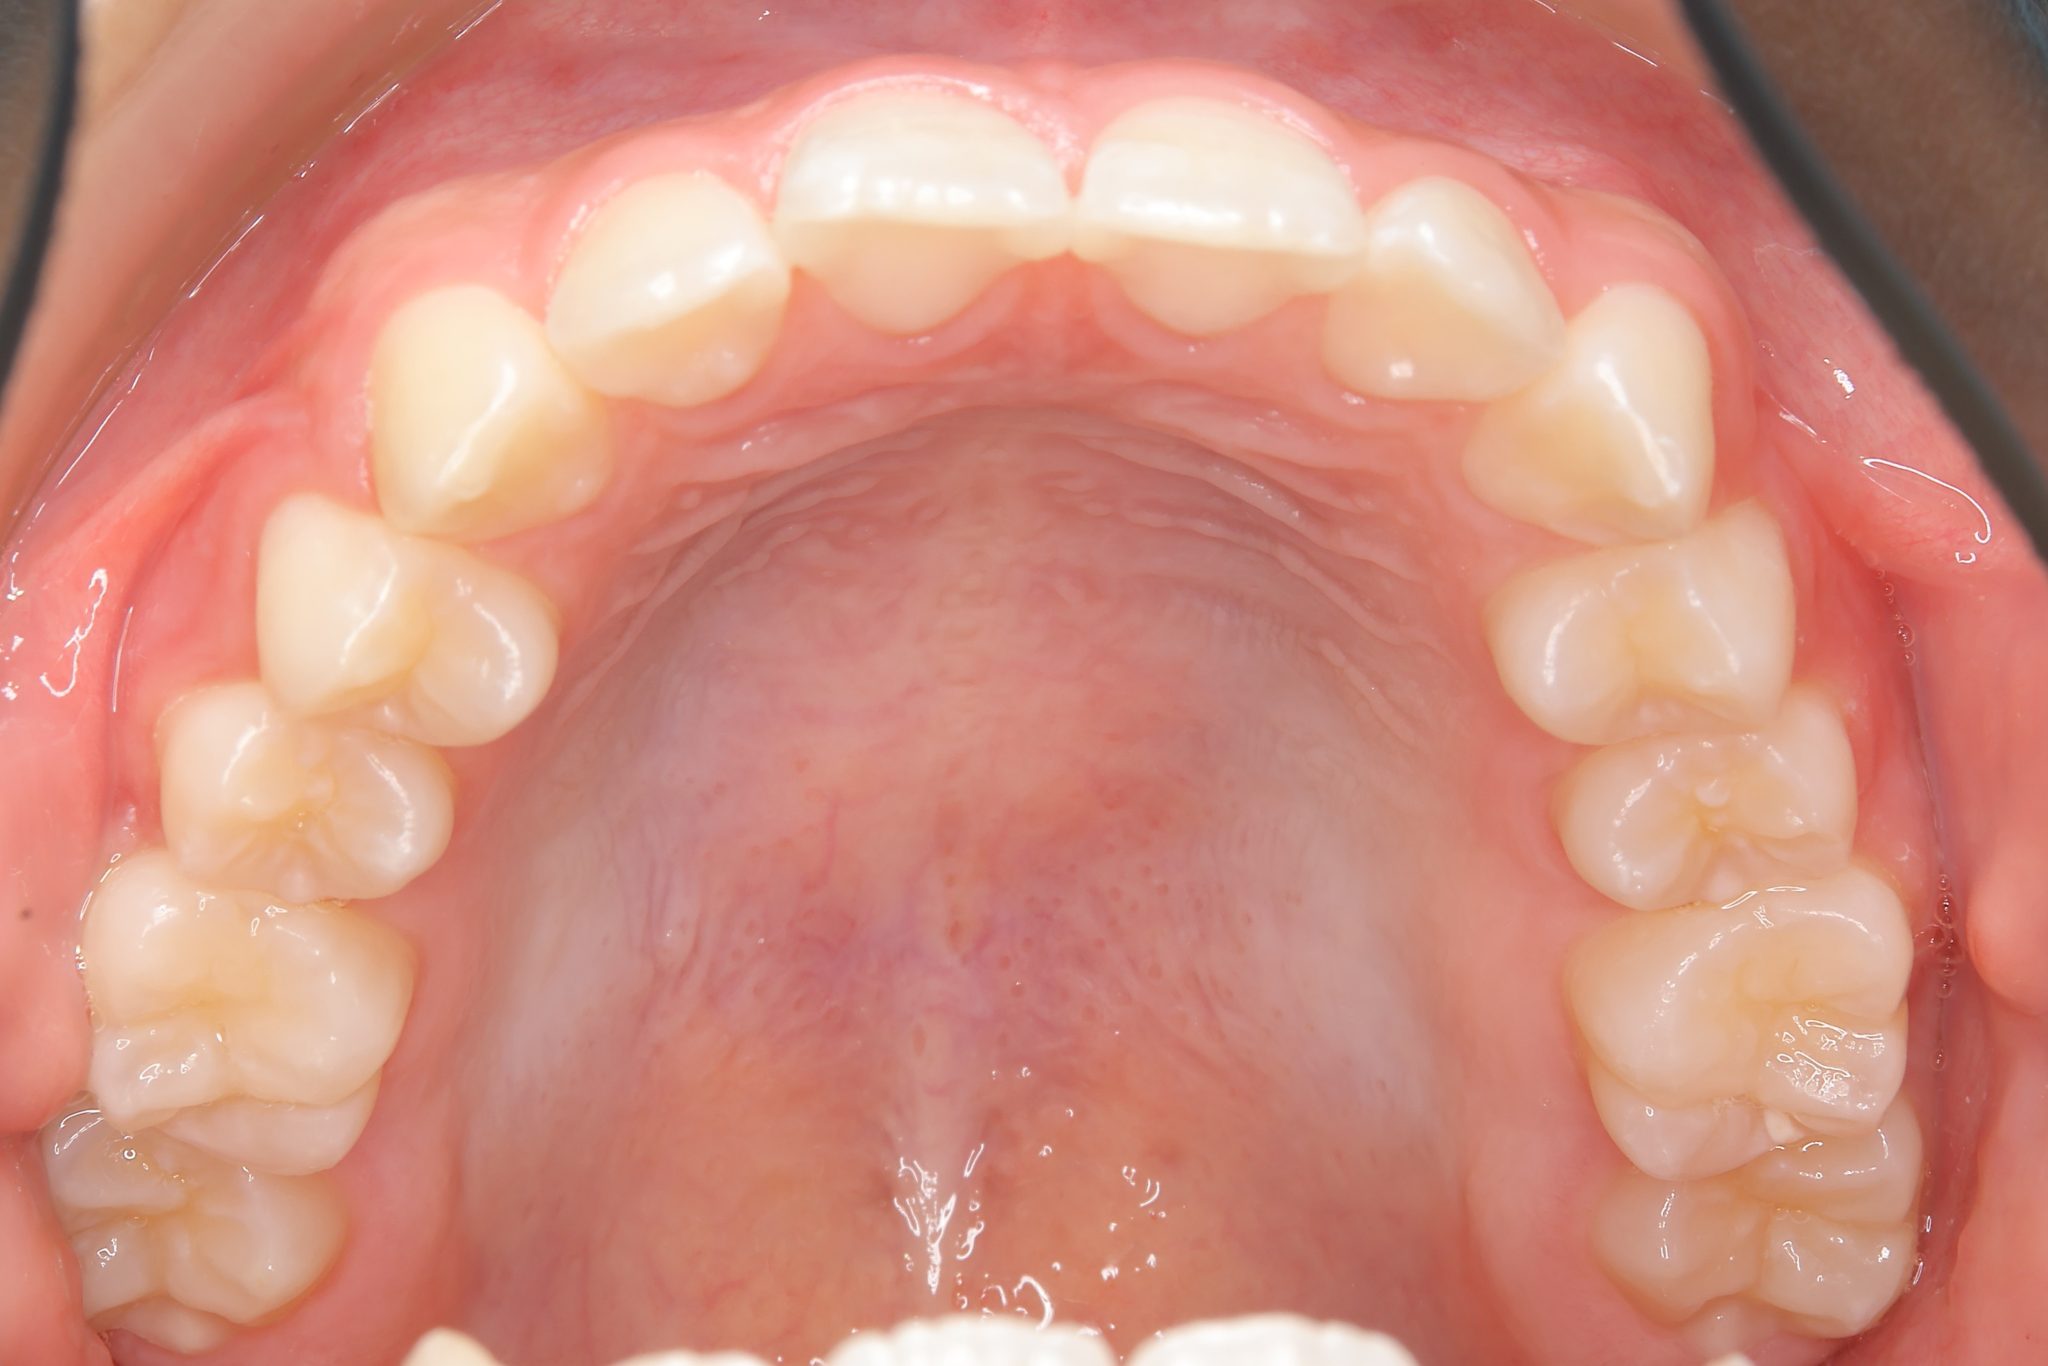

全顎ワイヤー矯正 症例_610 Case

ビフォー

| 主訴 | 前歯の歯並び|歯ぎしり |

| 施術内容 | 小児矯正1期治療 |

| 治癒期間 | 2年4か月間 |

| 費用 | 711,700円(税込) |

| リスク・副作用 | 違和感、不快感、痛み |